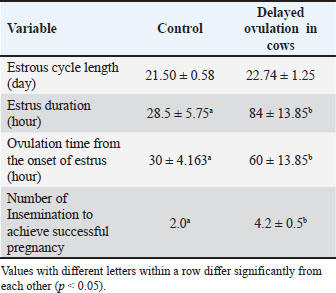

Table 1. Comparison of the reproductive cycle monitoring of Ongole crossbreed cows with and without delayed ovulation.